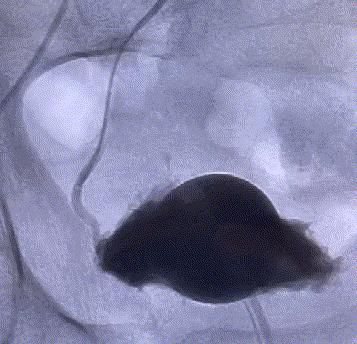

我院這項“很牛”的技術——介入下前列腺動脈超選擇栓塞術,能讓前列腺增生“由大變小”。該技術無須切開任何組織,僅通過股動脈穿刺置入微導管,經動脈的自然腔道,送達前列腺動脈,将PVA材料置于雙側前列腺動脈即可完成手術。其原理是阻斷前列腺營養供給,使其逐漸萎縮變小,從而解除對膀胱、尿道的壓迫,達到治療的目的。

該名來自梅塘鎮的62歲患者有前列腺增生多年,2年前就希望通過手術治療,無奈血糖始終控制不理想,不能電切手術治療。近期患者因排尿困難加重來院,經查仍有手術禁忌症,不适宜采用電切手術。爲了幫助患者擺脫疾病的困擾,李旭丹團隊決定給予采用“介入下前列腺動脈栓塞術”治療。

随後,李旭丹主任攜手胡志華主任爲患者實施介入治療,采用改良Seldinger法穿刺股動脈,在DSA引導下經動脈自然腔道,将微導管分别送達雙側髂内動脈進行造影,觀察雙側前列腺動脈分布情況,将微導管超選擇至雙側前列腺動脈,準确置入PVA栓塞材料,成功阻斷前列腺的營養供給,順利完成了治療。